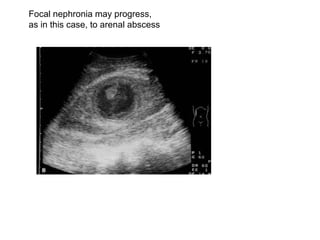

Focal pyelonephritis (lobar nephronia

Focal nephronia may progress,  as in this case, to arenal abscess